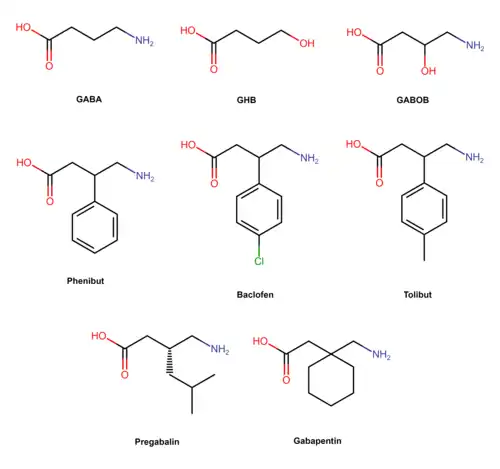

Gabapentinoids

Gabapentinoids are a unique and relatively novel class of depressants that selectively bind to the auxiliary α2δ subunit (CACNA2D1 and CACNA2D2) site of certain VDCCs and thereby act as inhibitors of α2δ subunit-containing voltage-gated calcium channels. α2δ is nicknamed the "gabapentin receptor". At physiologic or resting membrane potential, VDCCs are normally closed. They are activated (opened) at depolarized membrane potentials, which is the source of the "voltage-gated" epithet. Gabapentinoids bind to the α1 and α2 sites of the α2δ subunit family. Gabapentin is the prototypical gabapentinoid. The α2δ is found on L-type calcium channels, N-type calcium channels, P/Q-type calcium channels, and R-type calcium channels throughout the central and peripheral nervous systems. α2δ is located on presynaptic neurons and affects calcium channel trafficking and kinetics, initiates extracellular signaling cascades and gene expression, and promotes excitatory synaptogenesis through thrombospondin 1.[17] Gabapentinoids are not direct channel blockers; rather, they disrupt the regulatory function of α2δ and its interactions with other proteins. Most of the effects of gabapentinoids are mediated by the high-voltage activated N and P/Q-type calcium channels. P/Q-type calcium channels are mainly found in the cerebellum (Purkinje neurons), which may be responsible for the ataxic adverse effect of gabapentinoids, while N-type calcium channels are located throughout the central and peripheral nervous systems. N-type calcium channels are mainly responsible for the analgesic effects of gabapentinoids. Ziconotide, a non-gabapentinoid ω-conotoxin peptide, binds to the N-type calcium channels and has analgesic effects 1000 times stronger than morphine. Gabapentinoids are selective for the α2δ site but non-selective when they bind to the calcium channel complex. They act on the α2δ site to lower the release of many excitatory and pro-nociceptive neurochemicals, including glutamate, substance P, calcitonin gene-related peptide (CGRP), and more.[18][19][20]

Gabapentinoids are absorbed from the intestines mainly by the large neutral amino acid transporter 1 (LAT1, SLC7A5) and the excitatory amino acid transporter 3 (EAAT3). They are one of the few drugs that use these amino acid transporters. Gabapentinoids are structurally similar to the branched-chain amino acids L-leucine and L-isoleucine, both of which also bind to the α2δ site. Branched-chain amino acids like l-leucine, l-isoleucine, and l-valine have many functions in the central nervous system. They modify large neutral amino acid (LNAA) transport at the blood–brain barrier and reduce the synthesis of neurotransmitters derived from aromatic amino acids, notably serotonin from tryptophan and catecholamines from tyrosine and phenylalanine.[21] This may be relevant to the pharmacology of gabapentinoids.

Gabapentin was designed by researchers at Parke-Davis to be an analogue of the neurotransmitter GABA that could more easily cross the blood–brain barrier and was first described in 1975 by Satzinger and Hartenstein.[22][23] Gabapentin was first approved for epilepsy, mainly as an add-on treatment for partial seizures. Gabapentinoids are GABA analogues,[24] but they do not bind to the GABA receptors, convert into GABA or another GABA receptor agonist in vivo, or directly modulate GABA transport or metabolism.[25][26] Phenibut and baclofen, two structurally related compounds, are exceptions, as they mainly act on the GABA B receptor.[27][28] Gabapentin, but not pregabalin, has been found to activate voltage-gated potassium channels (KCNQ), which might potentiate its depressant qualities. Despite this, gabapentinoids mimic GABA activity by inhibiting neurotransmission.[29] Gabapentinoids prevent delivery of the calcium channels to the cell membrane and disrupt interactions of α2δ with NMDA receptors, AMPA receptors, neurexins, and thrombospondins. Some calcium channel blockers of the dihydropyridine class are used for hypertension to weakly block α2δ.[30]

Gabapentinoids have anxiolytic, anticonvulsant, antiallodynic, antinociceptive, and possibly muscle relaxant properties.[19][31][32] Pregabalin and gabapentin are used in epilepsy, mainly partial seizures (focal). Gabapentinoids are not effective for generalized seizures. They are also used for postherpetic neuralgia, neuropathic pain associated with diabetic neuropathy, fibromyalgia, generalized anxiety disorder, and restless legs syndrome.[33][34][35][36][37][38] Pregabalin and gabapentin have many off-label uses, including insomnia,[39] alcohol and opioid withdrawal,[40] smoking cessation,[41] social anxiety disorder,[42] bipolar disorder,[43][44] attention deficit hyperactivity disorder,[45] chronic pain, hot flashes,[46] tinnitus, migraines, and more. Baclofen is primarily used for the treatment of spastic movement disorders, especially in instances of spinal cord injury, cerebral palsy, and multiple sclerosis.[47] Phenibut is used in Russia, Ukraine, Belarus, and Latvia to treat anxiety and improve sleep, as in the treatment of insomnia.[48] It is also used for various other indications, including the treatment of asthenia, depression, alcoholism, alcohol withdrawal syndrome, post-traumatic stress disorder, stuttering, tics, vestibular disorders, Ménière's disease, dizziness, and the prevention of motion sickness and anxiety before or after surgical procedures or painful diagnostic tests.[48] Phenibut, like other GABAB receptor agonists, is also sometimes used by bodybuilders to increase the human growth hormone.

In some cases, gabapentinoids are abused and provide similar effects to alcohol, benzodiazepines, and gamma-hydroxybutyric acid (GHB).[49][50][51] The FDA placed a black box warning on Neurontin (gabapentin) and Lyrica (pregabalin) for serious breathing problems.[52] Mixing gabapentinoids with opioids, benzodiazepines, barbiturates, GHB, alcohol, or any other depressant is potentially deadly.[53][54][55][56]

Physical or physiological dependence does occur during the long-term use of gabapentinoids.[66] Following abrupt or rapid discontinuation of pregabalin and gabapentin, people report withdrawal symptoms like insomnia, headache, nausea, diarrhea, flu-like symptoms, anxiety, depression, pain, hyperhidrosis, seizures, psychomotor agitation, confusion, disorientation, and gastrointestinal complaints.[67][68] Acute withdrawal from baclofen and phenibut may also cause auditory and visual hallucinations, as well as acute psychosis.[69][70] Baclofen withdrawal can be more intense if it is administered intrathecally or for long periods of time. If baclofen or phenibut is used for long periods of time, it can resemble intense benzodiazepine, GHB, or alcohol withdrawal. To minimize withdrawal symptoms, baclofen or phenibut should be tapered down slowly. Abrupt withdrawal from phenibut or baclofen could possibly be life-threatening because of its mechanism of action. Abrupt withdrawal can cause rebound seizures and severe agitation.[71][70]